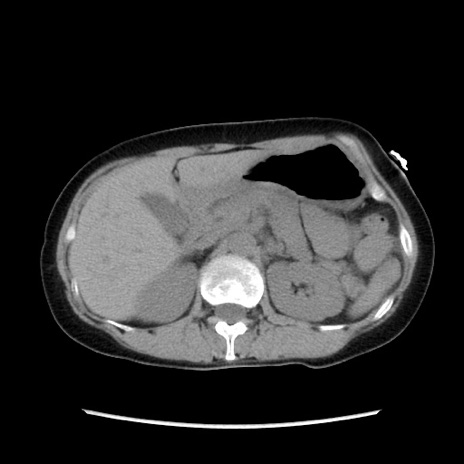

冠状断像

【症例】40歳代 女性

【主訴】上腹部痛、嘔気・嘔吐

【現病歴】約9時間前頃から急に上腹部痛、嘔気、嘔吐が出現。改善しないため救急要請。

【既往歴】子宮頚癌(広汎子宮全摘術、放射線療法)、腸閉塞

【身体所見】腹部:平坦、軟、腸雑音亢進、上腹部を中心に腹部全体に圧痛あり。

【データ】WBC 8400、CRP 0.03